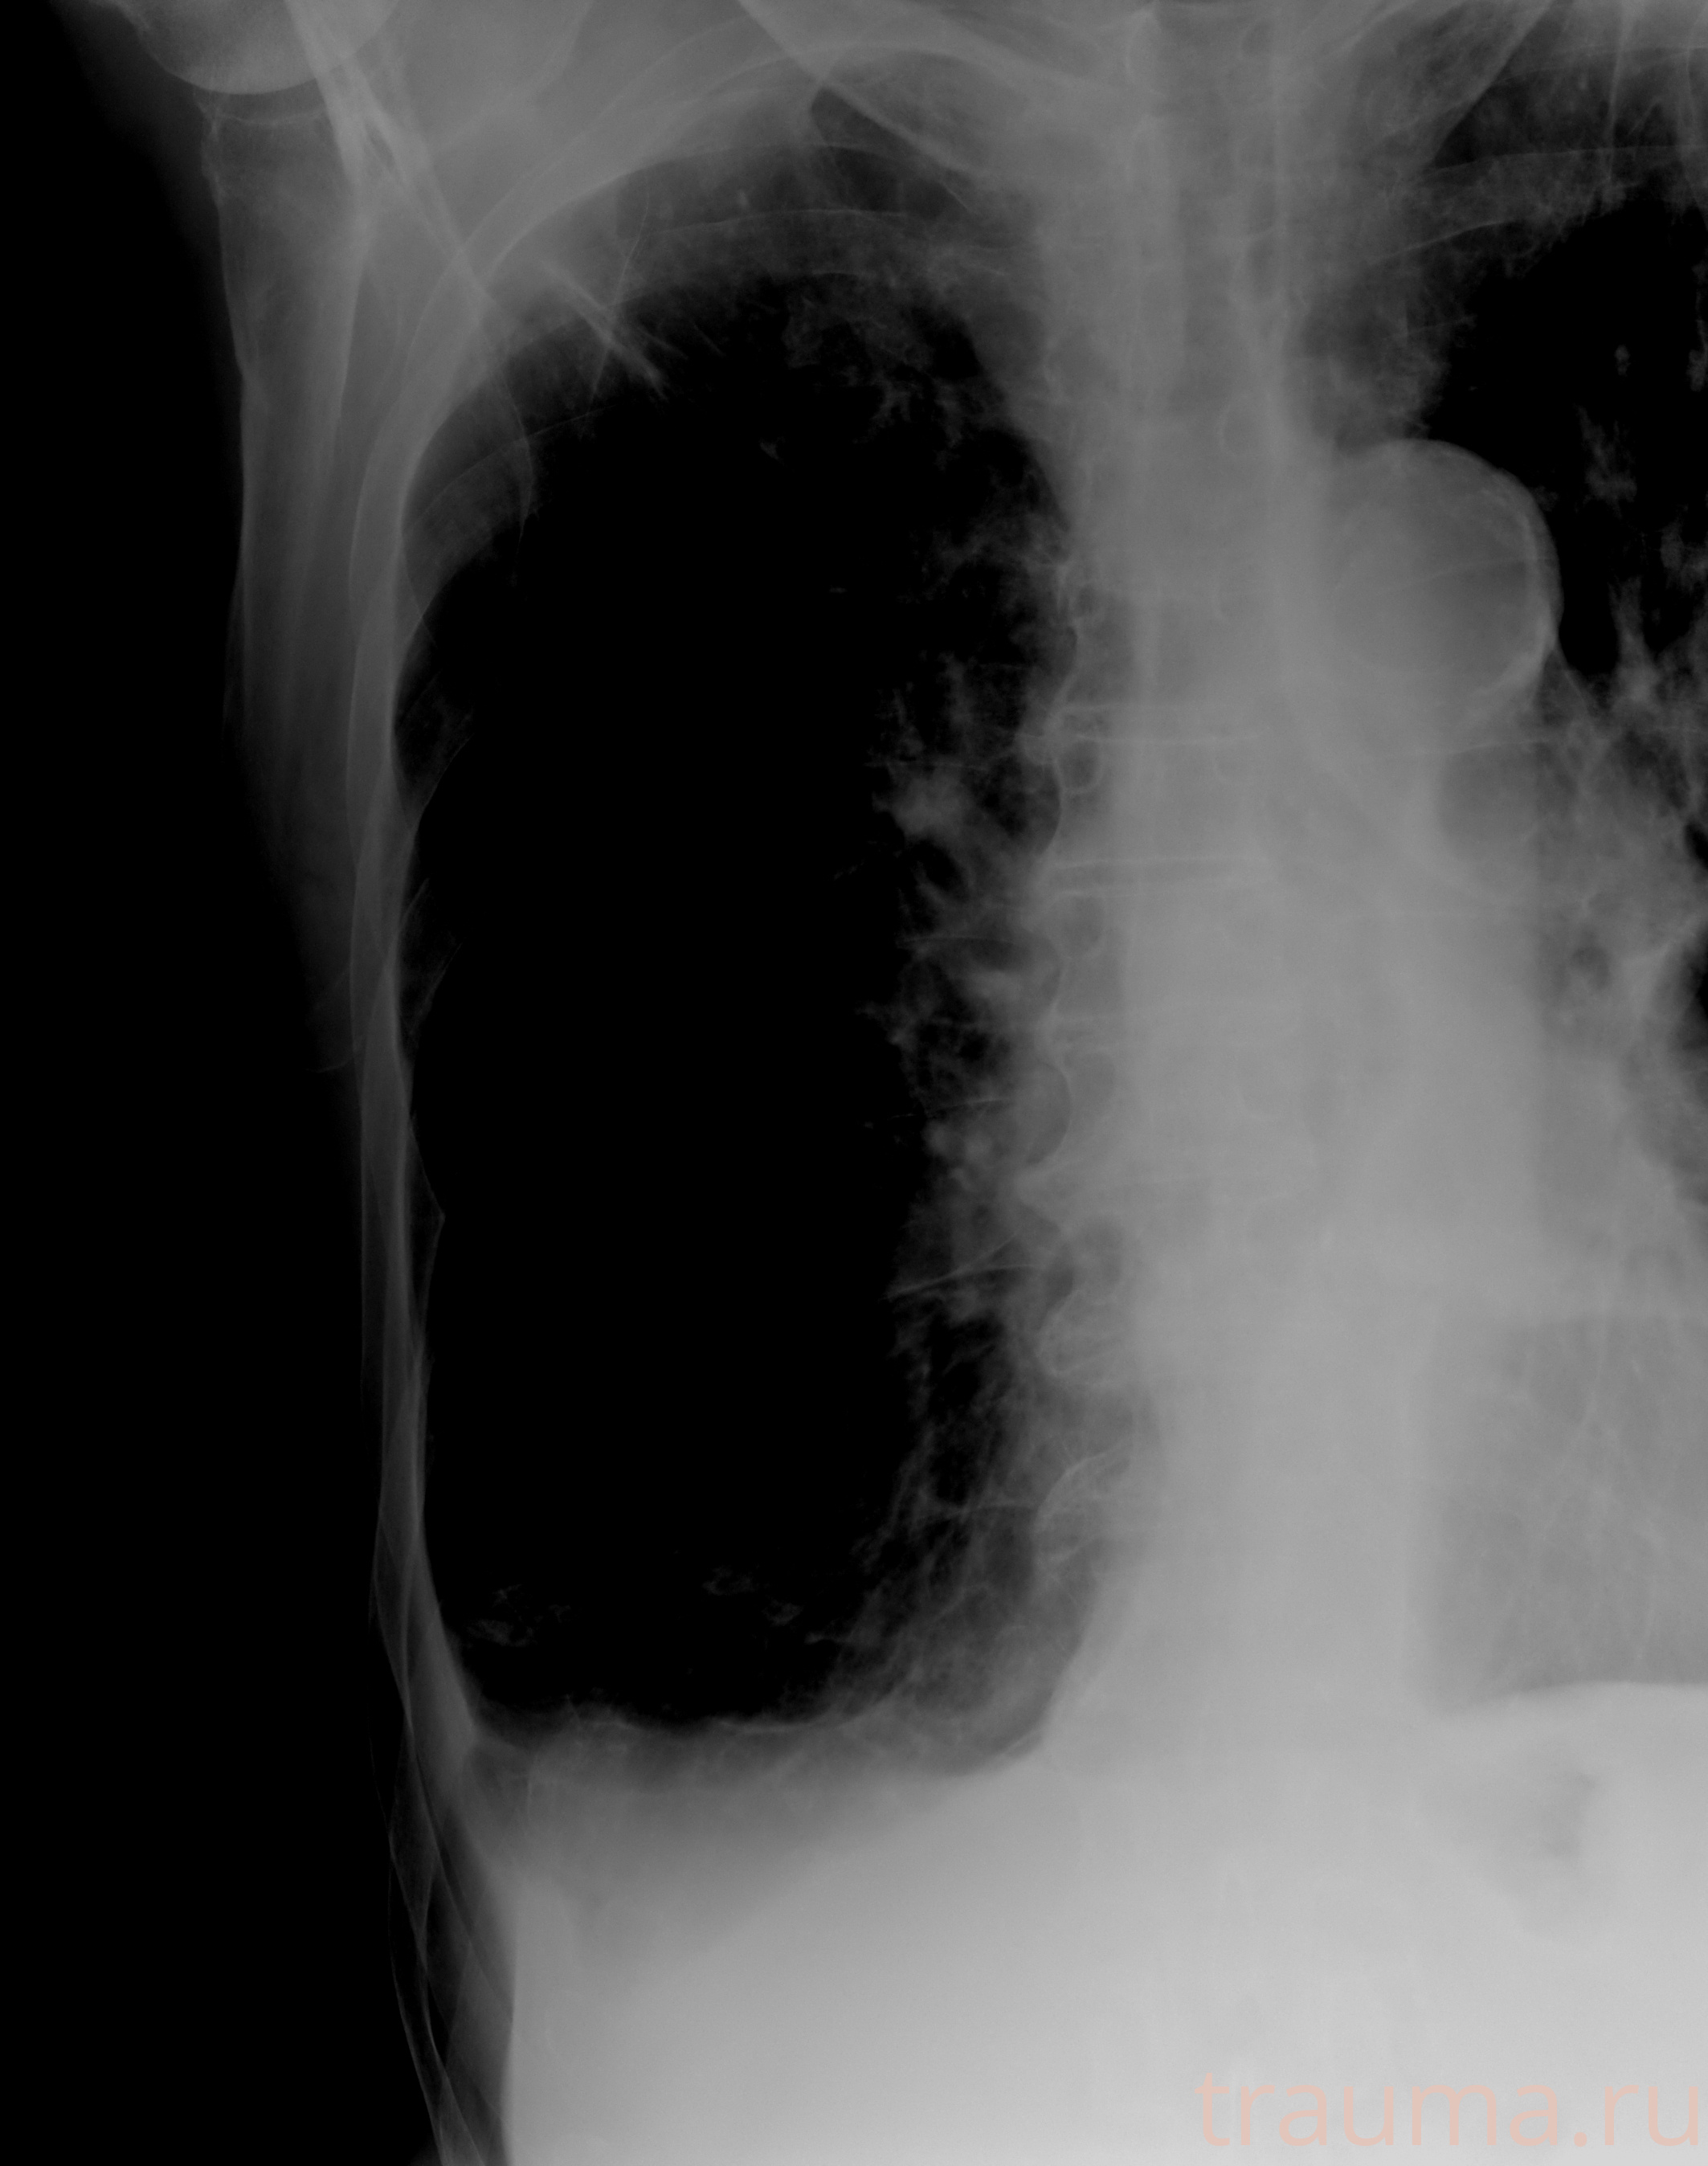

Рентген на дому: по вашему адресу приезжает врач-рентгенолог, травматолог-ортопед с мобильным рентгеновским аппаратом, проводит диагностику травмы или заболевания, делает необходимые рентгенограммы, дает рекомендации по дальнейшему лечению. Получить качественные снимки в домашних условиях возможно благодаря уникальной методике, разработанной МосРентген Центром для института  Склифосовского